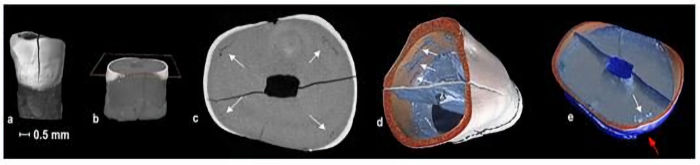

Micro-CT scan shows internal defects in one of the teeth found at the St Mary’s cemetery. Credit: Flinders University

A micro-CT scan shows an external defect in a section of a tooth. Credit: Adelaide Microscopy

Tooth micro-scans taken as part of the PhD investigation at the Adelaide Microscopy. Credit: Flinders University